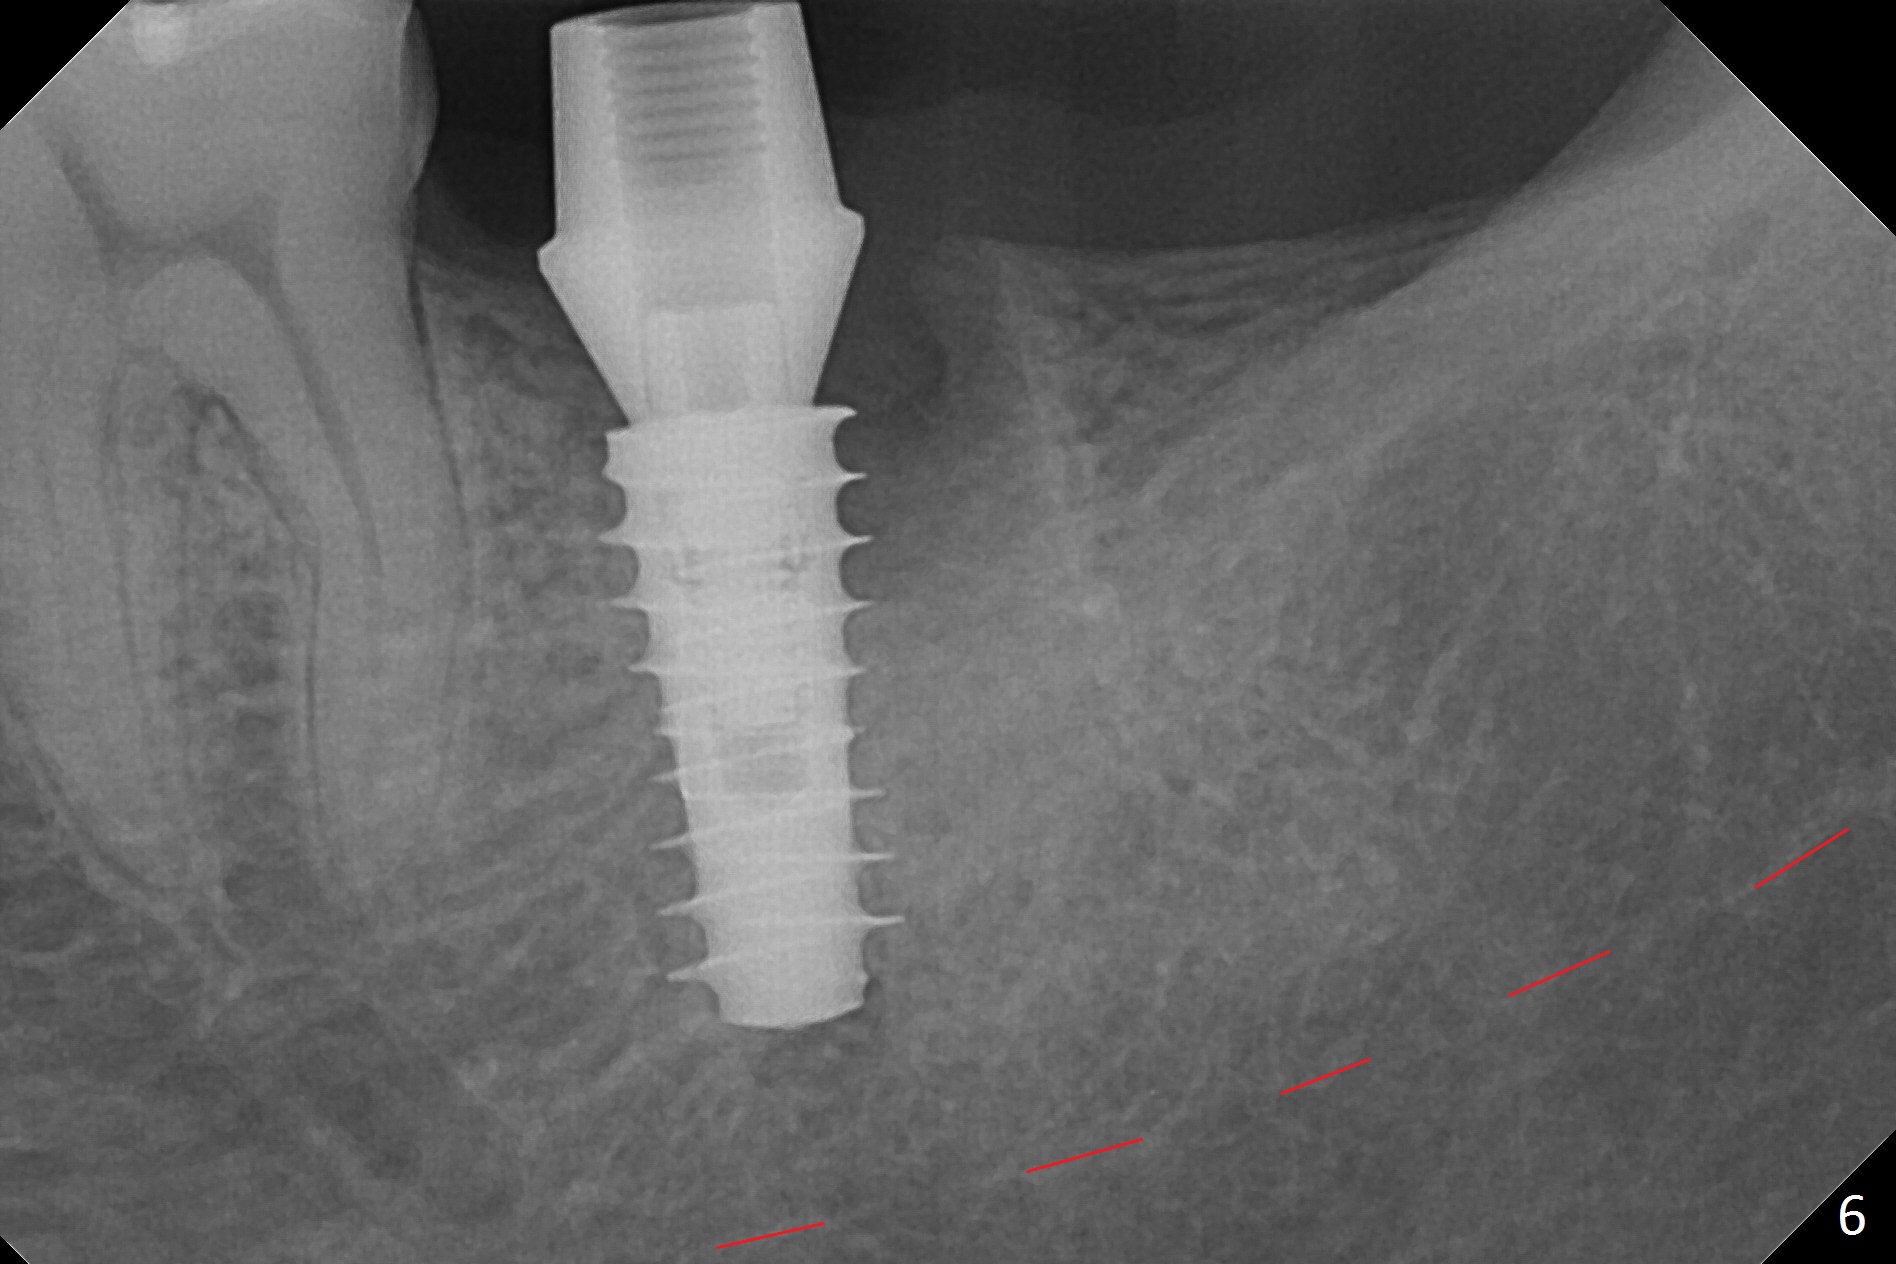

Following 4.8 mm MD, a 5x11 mm IBS implant is placed subcrestal circumferentially (Fig.6 with 50 Ncm).